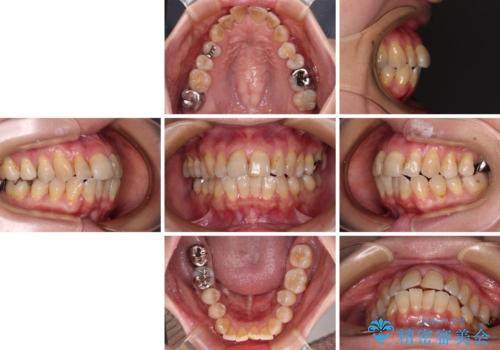

【モニター】前歯の突出感を抜歯矯正で改善

- 30代女性

- 治療期間

- 1年7ヶ月

- 口元の突出感を気にして来院された患者様です。

上下前歯が著しく前突している状態であったので、上下左右の小臼歯4本を抜歯し、ワイヤー装置にて矯正治療を行うこととしました。

上顎左側は第二小臼歯に大きなむし歯があったため、通常は第一小臼歯を抜歯するところ、イレギュラーに第二小臼歯を抜歯することとしました。

抜歯する第二小臼歯の後方の歯は神経近くにまで及ぶむし歯があったため、事前に処置をしておき、矯正治療後にオールセラミッククラウンにて補綴治療を行うこととしました。